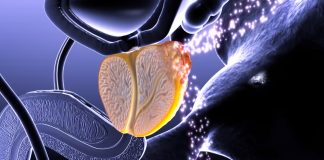

পরীক্ষা সফল হলে তৈরি হবে ক্যান্সারের টিকা!

মারণ ব্যাধি ক্যান্সারে ভুগছে অসংখ্য মানুষ। পৃথিবীতে সবচেয়ে বিপজ্জনক রোগের মধ্যে একটি হলো ক্যান্সার। এখনও পর্যন্ত এ রোগের কোন ওষুধ আবিষ্কার হয়নি যা...